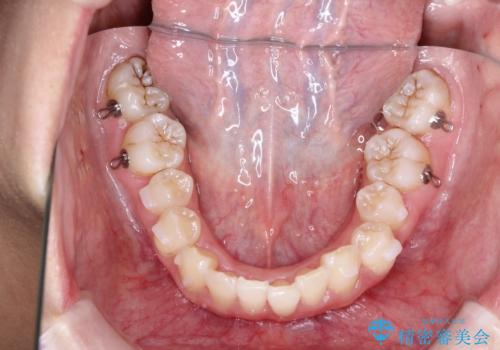

このケースでは非抜歯にて奥歯を後方に移動させる事で前歯の突出を改善するスペースを作り出していますが、これはマウスピースと顎間ゴムの併用によるもので、患者様のご協力の賜物と言えます。

深い噛み合わせについてはシミュレーション上の結果と、予期される実際の歯の移動量とを考慮し、特殊なセットアップを行う事で望ましい結果を得ることができました。

治療途中でリファインメントという追加のマウスピースを製作する手順を行っていますが、その際に上下の正中を合わせたいとの要望があったため、追加シミュレーションの際に追加でセットアップを施しましたが、無事、上下の正中もご要望通りに改善しています。

使用した装置はマウスピースと顎間ゴムのみです。ワイヤーやマイクロインプラントなど補助装置の使用はありません。